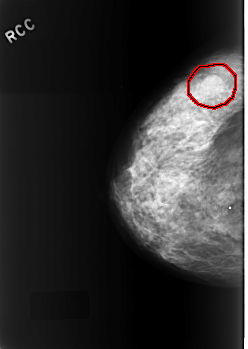

FILE: C_0337_1.RIGHT_CC.OVERLAY

TOTAL_ABNORMALITIES 1

ABNORMALITY 1

LESION_TYPE MASS SHAPE OVAL MARGINS OBSCURED

ASSESSMENT 3

SUBTLETY 5

PATHOLOGY BENIGN

TOTAL_OUTLINES 1

BOUNDARY